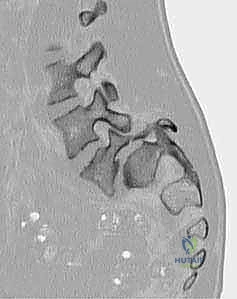

2. المفصل القطني العجزي (L5-S1)

هذا المفصل هو نقطة التقاء آخر فقرة في العمود الفقري القطني (L5) مع أول فقرة ملتحمة في عظم العجز (S1). هذا الموقع هو الأكثر عرضة للانزلاق الفقاري على الإطلاق. لماذا؟ لأن هذا المفصل يتحمل الجزء الأكبر من وزن الجزء العلوي من الجسم، بالإضافة إلى أنه يقع في نقطة انتقال منحنى العمود الفقري، مما يجعله عرضة لضغوط ميكانيكية هائلة (قوى القص).

في الحالات المزمنة، وبسبب الاحتكاك المستمر، يمكن أن يتغير شكل العظام؛ حيث يصبح السطح العلوي للعجز (S1) على شكل قبة أو محدباً، بينما يصبح السطح السفلي للفقرة (L5) مقعراً، وقد يبرز عند زاويته الأمامية السفلية، مما يزيد من تعقيد الحالة.

التصوير المقطعي المحوسب (CT Scan):

يوفر تفاصيل دقيقة للغاية عن البنية العظمية. يُستخدم بشكل خاص لتقييم العيوب العظمية بدقة (مثل كسر البرزخ المفصلي)، وللتخطيط الجراحي الدقيق قبل إجراء عملية التثبيت.